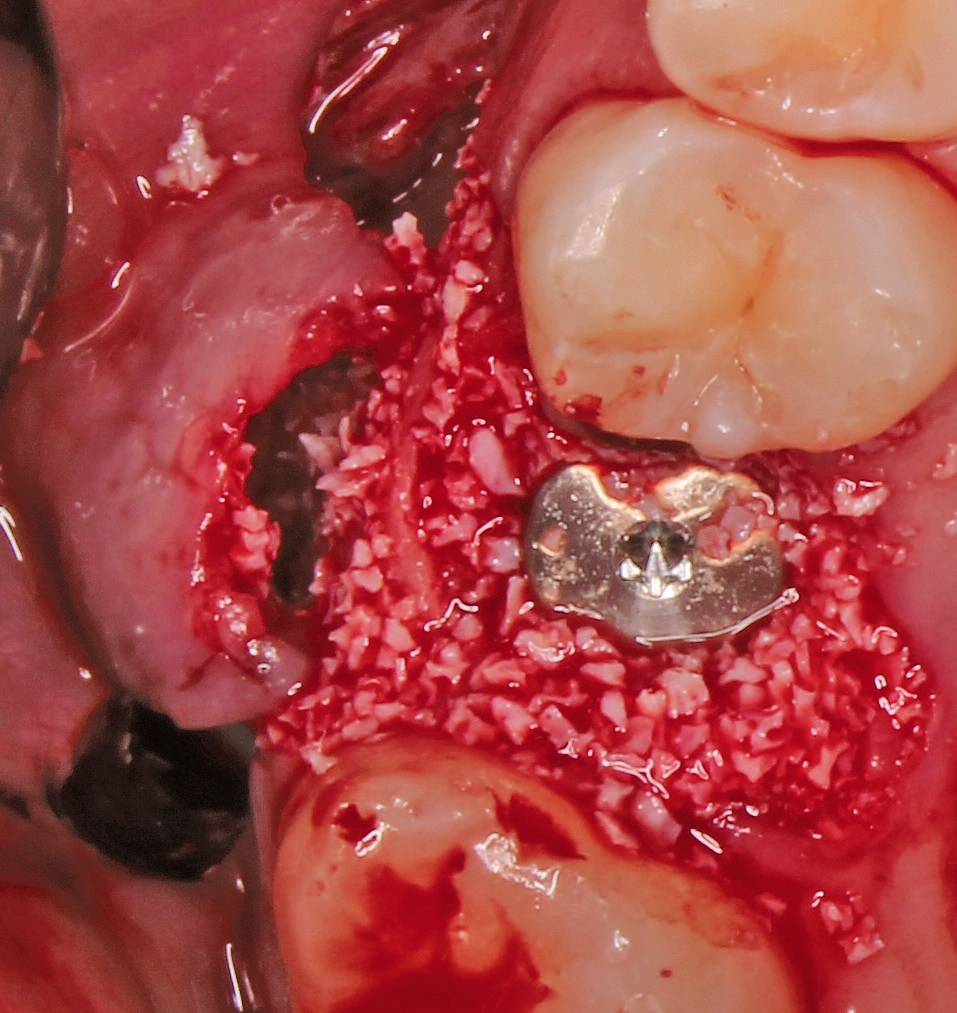

Nach der Präparation des Weichgewebes wurde ein Mukoperiostlappen mit Hilfe der Instrumentenspitze PR2 (Piezosurgery, Mectron, I-Genua) vorsichtig präpariert, um eine suffiziente Deckung der Wunde zu gewährleisten (Abb. 9 und 10). Nach Vorbereitung des Weichgewebes wurde die 3D-gedruckte Bohrschablone auf den Zahnbogen gesetzt und ein Führungsschlüssel mit 2 mm Durchmesser eingesetzt, durch den ein Osteotom einführt wurde, um eine Führung für den nachfolgenden Trepanbohrer in den Knochen kondensierend zu präparieren (Abb. 11). Entlang des Führungskanals wurde das Bett für den allogenen Knochenring (maxgraft bonering; botiss biomaterials GmbH, Berlin) trepaniert (Abb. 12). Der allogene Knochenring wurde extraoral passgenau zugeschnitten und anschließend in die Extrationsalveole platziert (Abb. 13 und 14). Mittels eines breiten Osteotoms wurde der Knochenring samt basalem Knochensegment schablonengestützt nach apikal in den Sinus maxillaris verschoben. Ein parallelwandiges Implantat (Bone Level Roxolid, SLActive, Straumann) mit einem Durchmesser von 4,1 mm und einer Länge von 10 mm wurde zentral in den positionsstabilen Knochenring primärstabil inseriert, mit einer Fixierungkappe (Durchmesser 5,5 mm) versehen und die umliegende Extrationsalveole mit granulärem bovinem Knochenersatzmaterial ausgefüllt (Abb. 15-17). Anschließend wurde die Wunde mit dem Mukoperiostallappen gedeckt und speicheldicht vernäht (Abb. 18). Zur postoperativen Kontrolle wurde ein Orthopantomogramm aufgenommen, auf dem keinerlei Verletzungen benachbarter anatomischer Strukturen zu erkennen sind (Abb. 19). Es folgten zwei radiologische Verlaufskontrollen, vier und sechs Monate nach dem Eingriff, ohne Besonderheiten (Abb. 20 und 21).